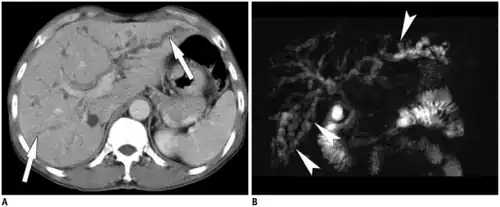

Typical imaging features center around imaging of the liver with CT, ultrasound, or MRI for detection of primary biliary cirrhosis. Traits that raise suspicion for the infection include intra- and extrahepatic dilatation and structures with intraductal pigmented stones, usually in the absence of gallstones and with regions of segmental liver atrophy, particularly the lateral aspect of the left hepatic lobe. Also, reduced arborization of peripheral ducts is seen. A full 5% of chronic infections go on to develop cholangiocarcinoma.[28]

- ↑ Park, MS; Yu, JS; Kim, KW; Kim, MJ; Chung, JP; Yoon, SW; Chung, JJ; Lee, JT; Yoo, HS (September 2001). "Recurrent pyogenic cholangitis: comparison between MR cholangiography and direct cholangiography". Radiology. 220 (3): 677–82. doi:10.1148/radiol.2202001252. PMID 11526266.